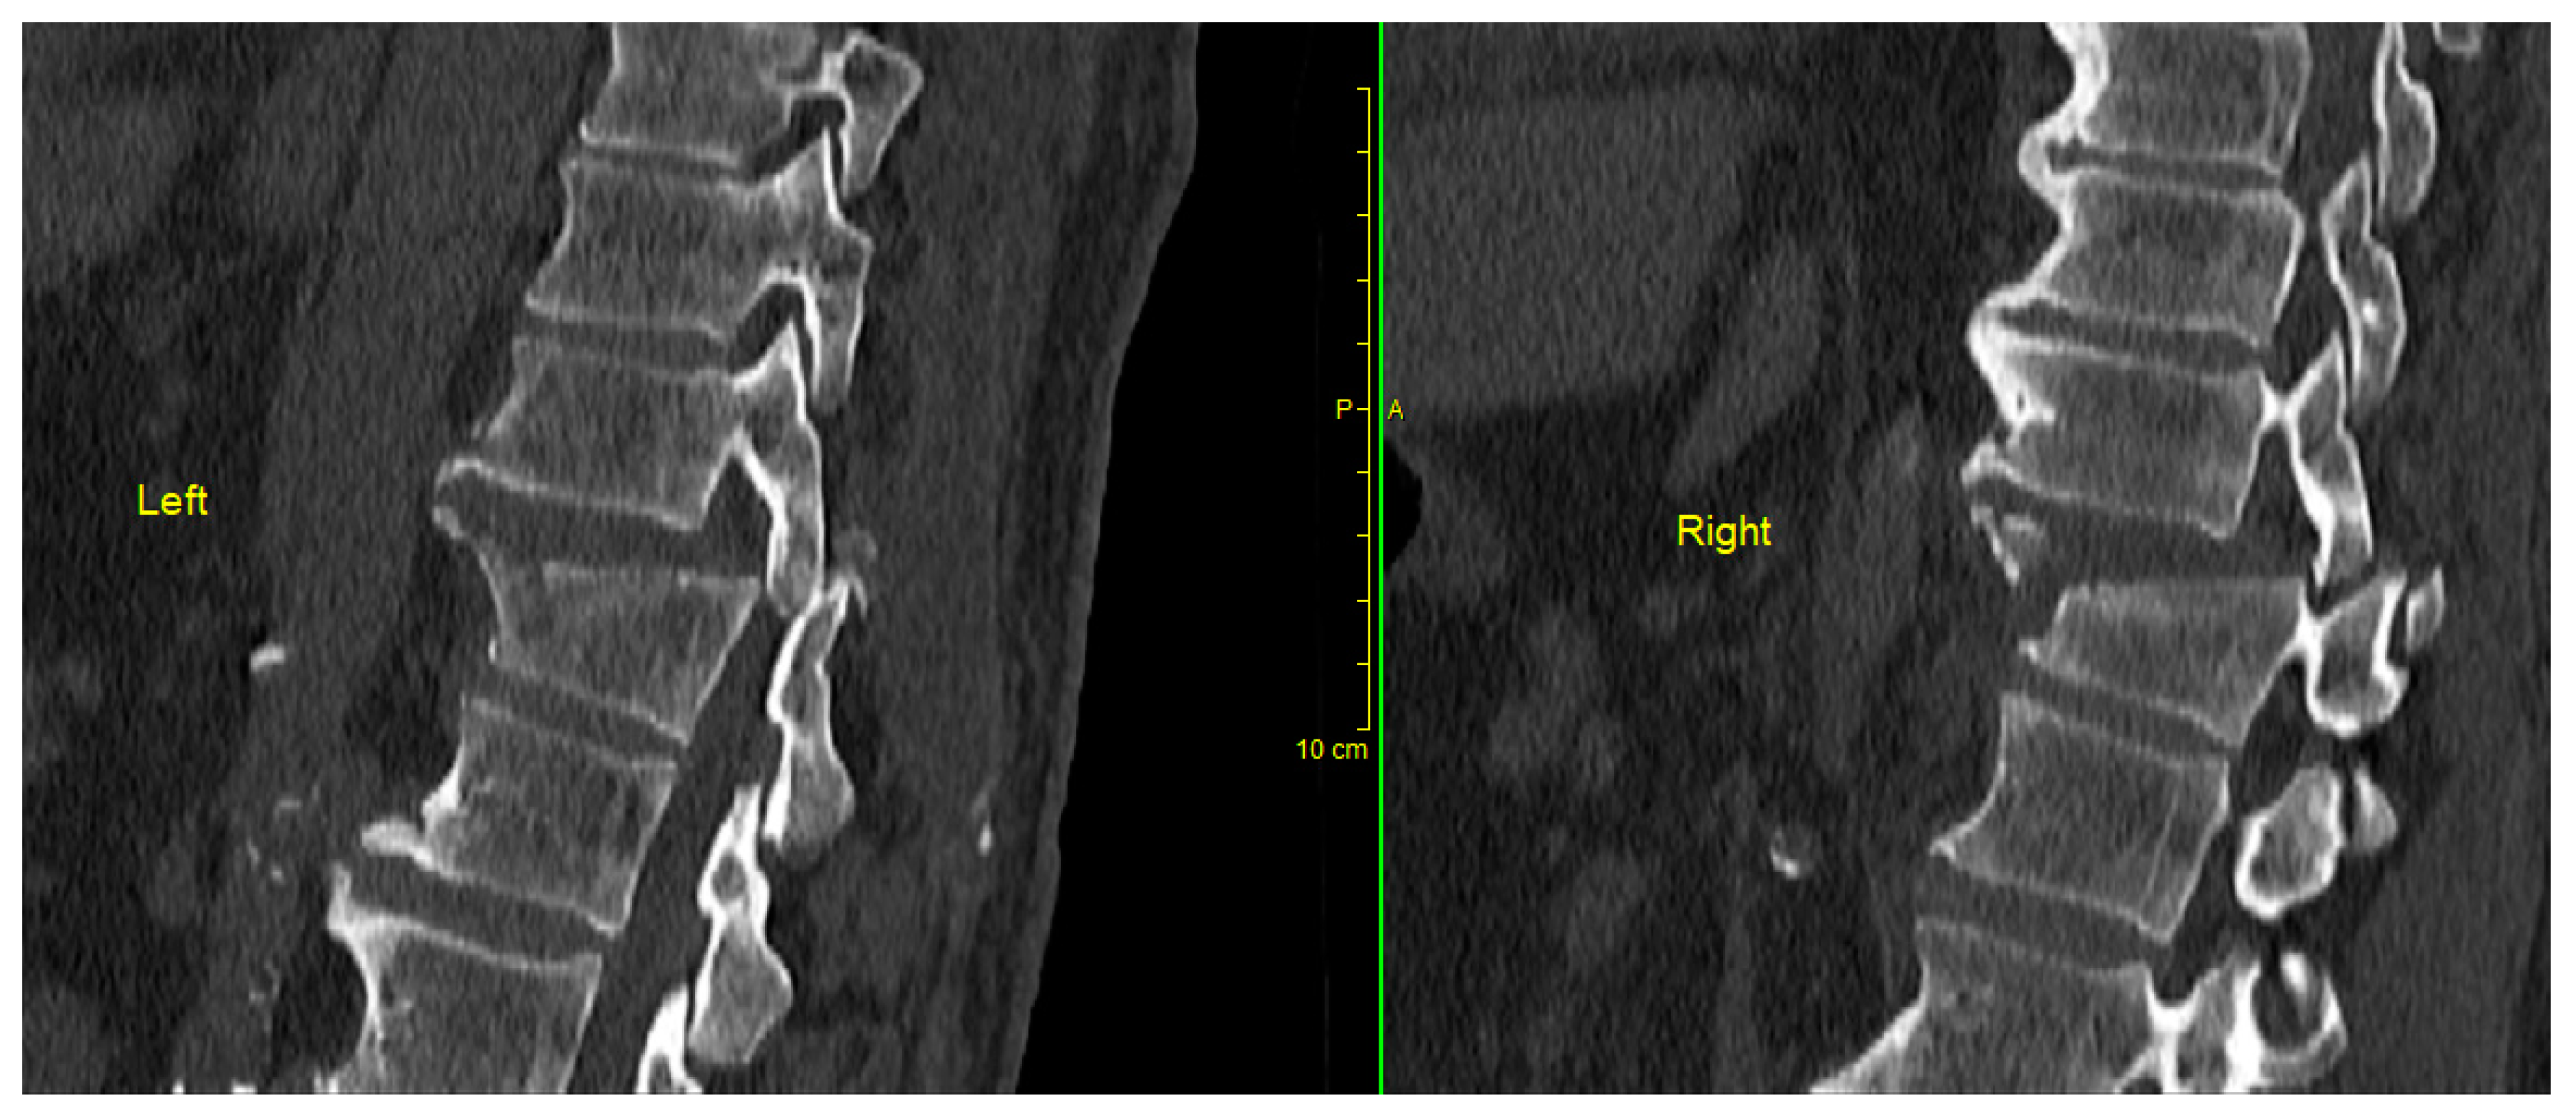

The junctional thoracic segment spanning from Th10 to T12 often experiences trauma due to its unique biomechanical properties. This particular region, frequently known as the junction between the thoracic and lumbar spine, is particularly vulnerable to injury. This vulnerability arises from its role as a transitional area, transitioning from the sturdy and relatively immobile thoracic spine, which is anchored by ribs on both sides, to the more flexible lumbar spine below. Thoracolumbar fracture–dislocations (AO type C injuries) are rare injuries that occur due to high-energy trauma, and the result is translational and rotational instability of the spinal column, as well as severe neurological impairment (Figure 1 and Figure 2) [1]. Thoracic and thoracolumbar fractures with bilateral dislocation and locking of the facet joint are rare and challenging fracture types for correction and management by surgical treatment (Figure 3). As a general guideline, surgical intervention is typically recommended for unstable spinal injuries, including flexion-distraction injuries, unstable burst fractures, and fracture–dislocations. While surgery can alleviate pain and facilitate early mobilization and rehabilitation, there is no discernible disparity in terms of neurological recovery and long-term functional outcomes between surgical and non-surgical treatments [2].

Figure 2.

Preoperative CT scan showing a bilateral locked facet fracture–dislocation of the Th11–Th12 levels. The tips of the superior facet joints were also fractured indicating the high violence of the injury causing bilateral locked facet dislocation.